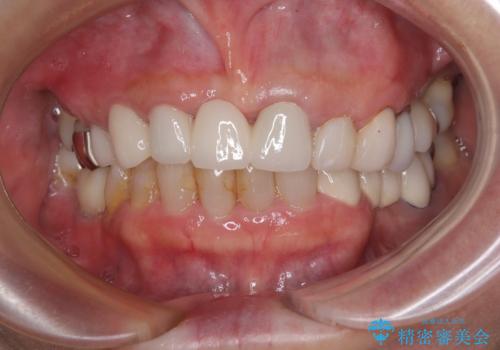

周辺の歯は20年以上前に装着したクラウンで、色合いや形態が気になっているとのことで、オールセラミックブリッジにて補綴治療を行うこととしました。

まずは土台の歯を引っぱり出し、外科処置により歯肉の状態を十分に整えた上で、オールセラミッククラウンにて補綴することとしました。

元々の土台は歯肉の中に埋もれており、歯肉が著しく腫れている状態だったため、歯を引っぱり出すこととしました。引っぱる期間は2ヶ月ほどで済み、その後歯周外科処置を行ったことで、土台周りの歯肉は腫脹のない健全な状態へと改善されました。